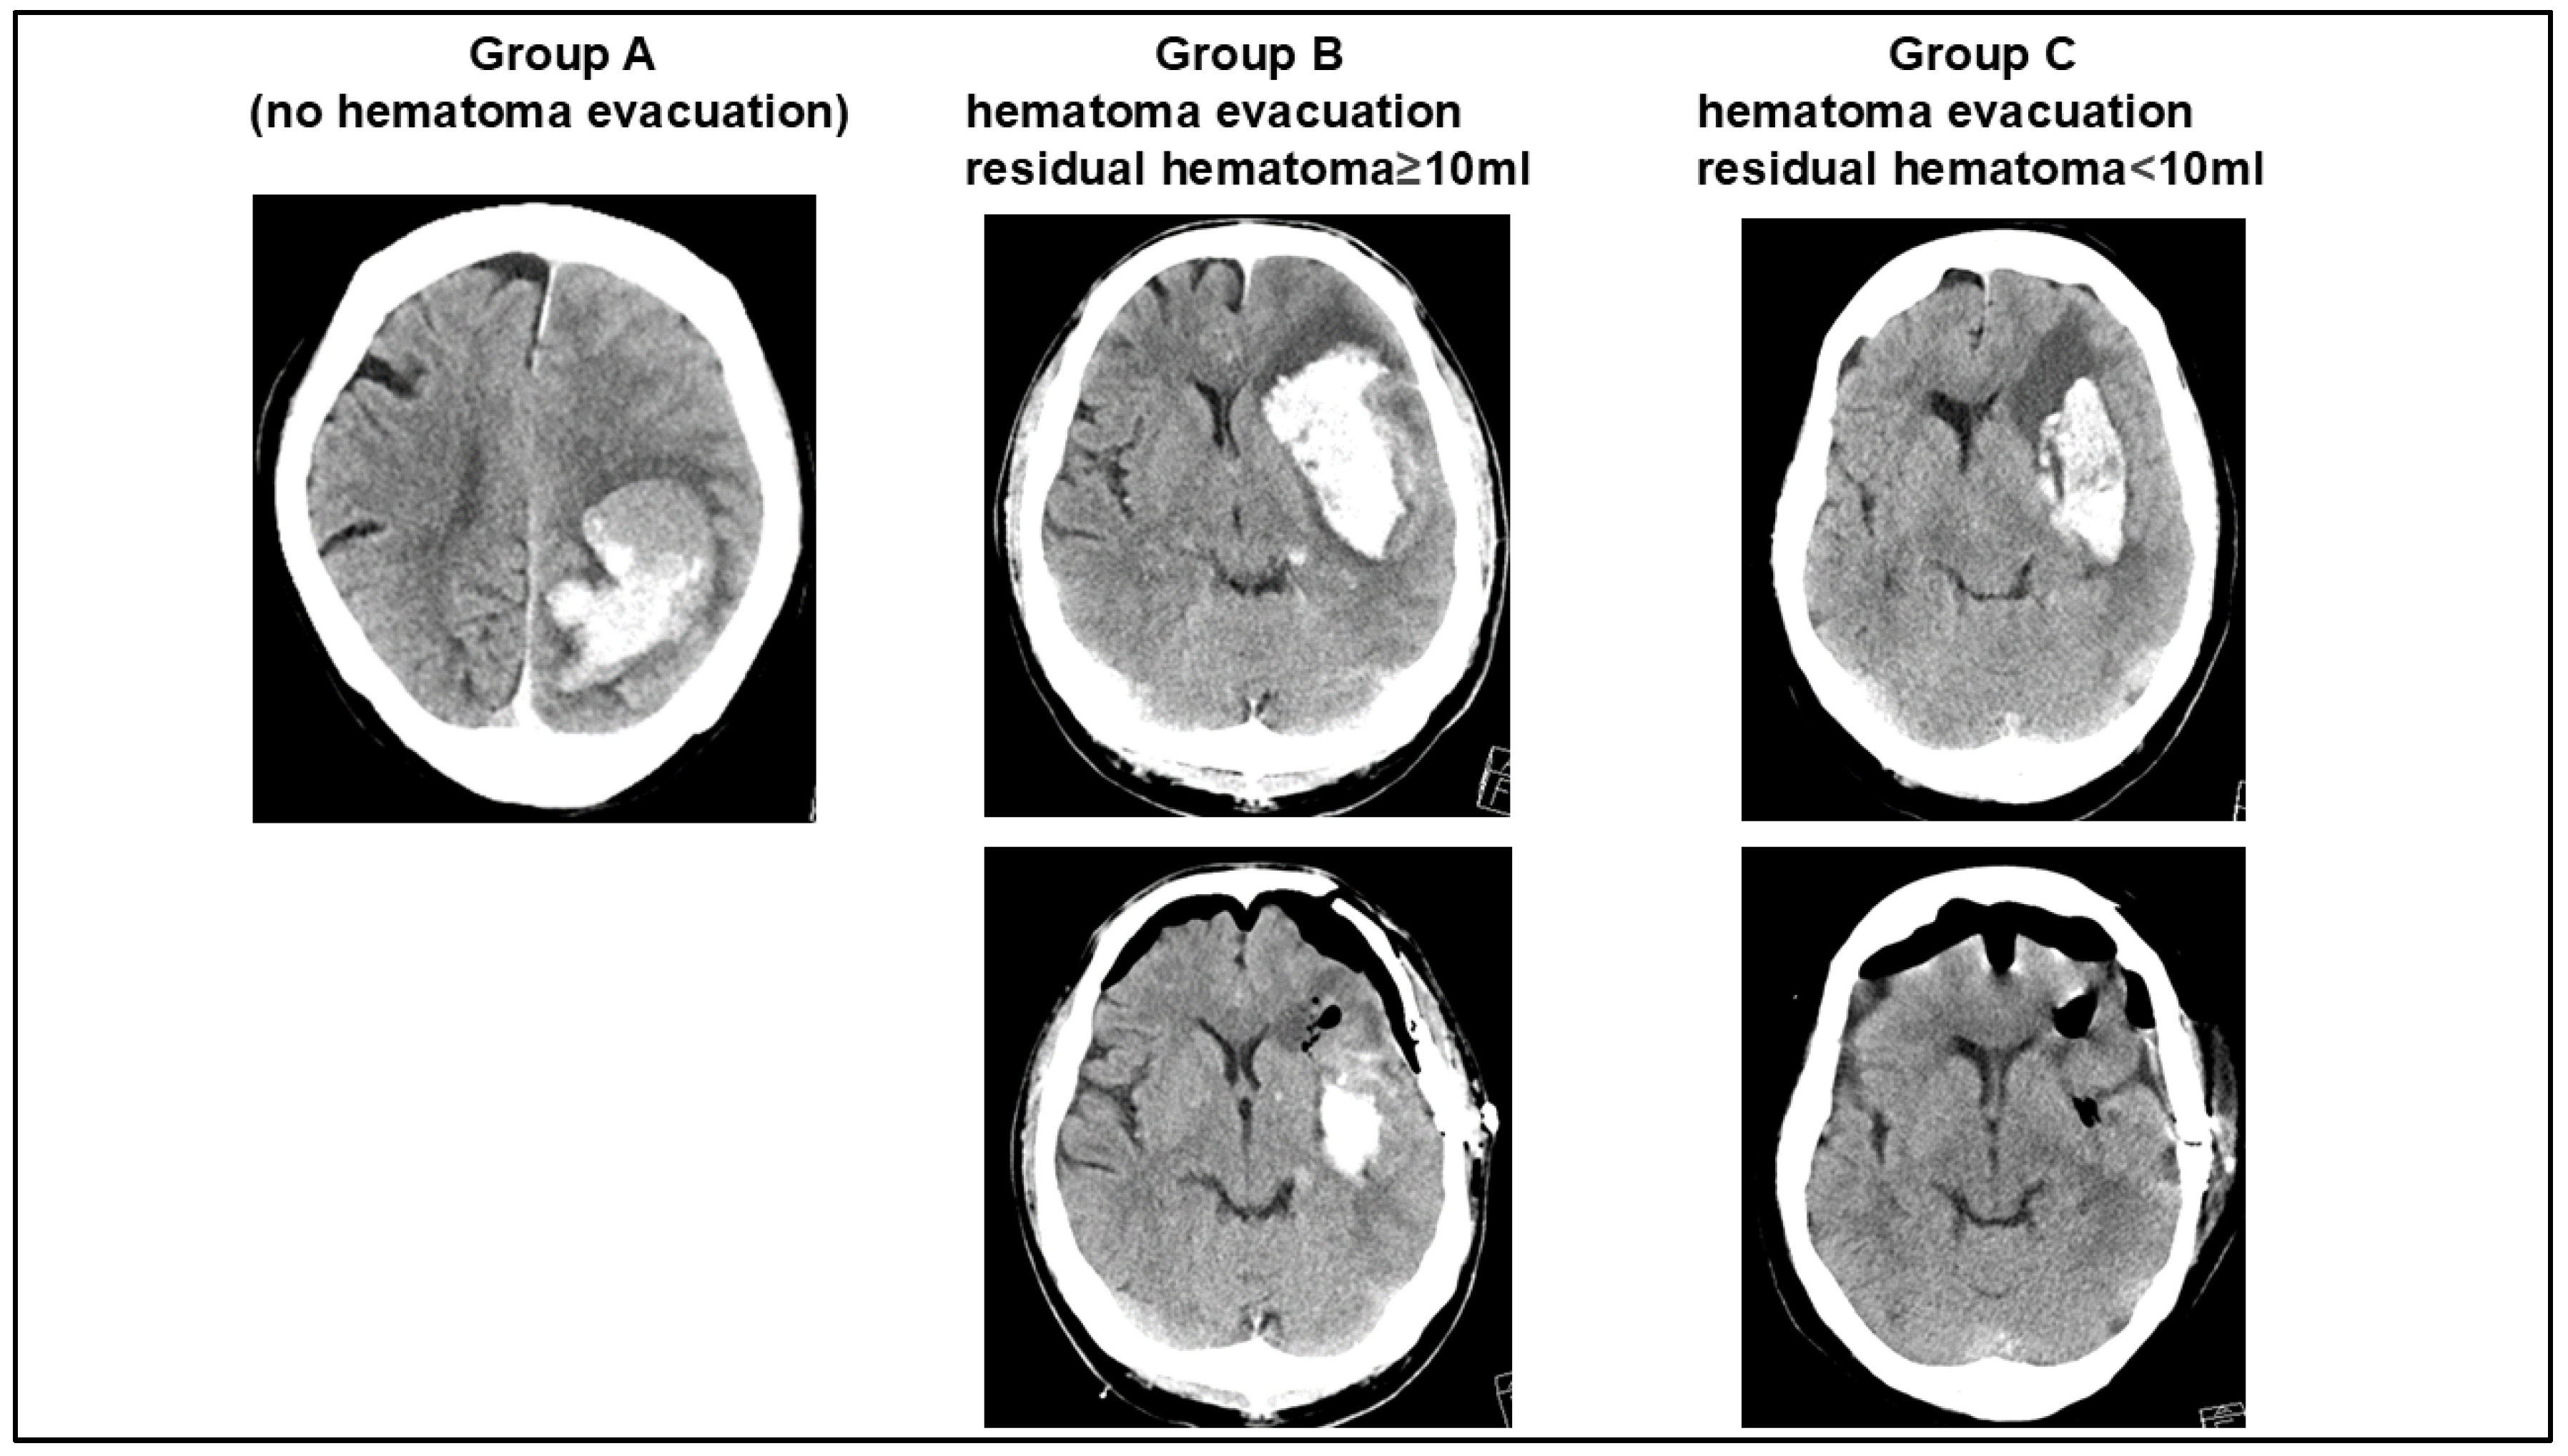

| Group A | Group B | Group C | p | |

|---|---|---|---|---|

| without hematoma evacuation | hematoma evacuation with residual hematoma ≥ 10 mL | hematoma evacuation with residual hematoma < 10 mL | ||

| Number of patients | 88 | 25 | 61 | NA |

| Radiological findings | ||||

| hematoma volume (mL) | 26.4 ± 5.2 | 42.2 ± 9.9 | 43.2 ± 9.1 | <0.01 |

| residual hematoma (mL) | NA | 16.8 ± 4.5 | 4.8 ± 3.1 | <0.01 |